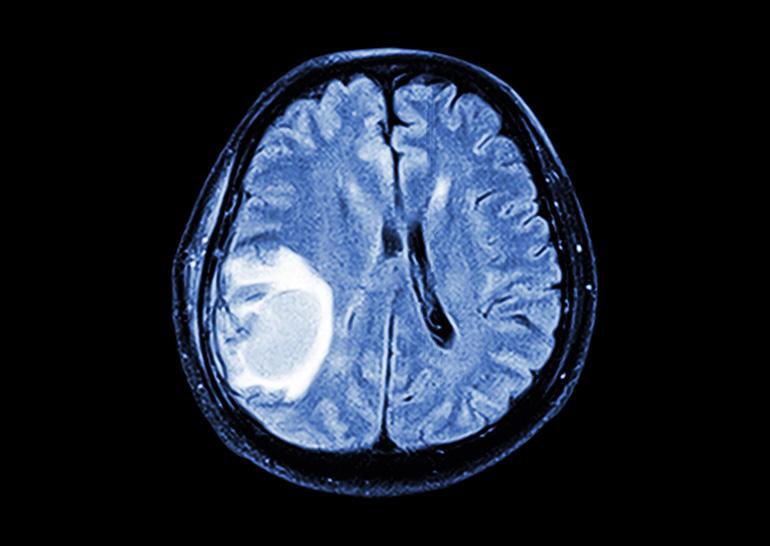

После этого резко снижается активность Emx2. Было выдвинуто предположение, что ген можно использовать в борьбе против глиобластом, так как подобные опухоли похожи на совокупности астроцитов – астроглии. Как показали эксперименты на клеточных культурах, активация Emx2 эффективно предотвращает рост злокачественных клеток.

Позднее ученые провели эксперименты на мышах, причем медикам удалось отыскать участок ДНК, ответственный за активацию Emx2 исключительно в злокачественных клетках. Итог тестов показал, что новая терапия успешно справилась с четырьмя разновидностями глиобластомы. Здоровые клетки при этом остались неповрежденными.